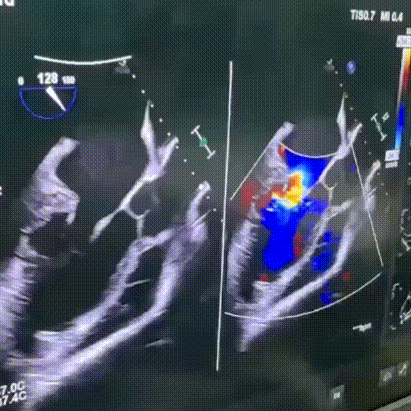

食道超声示长轴界面泵头基本对着二尖瓣,调节辅助装置的泵速,证实血流方向正常,流速可。

关胸前转速优化食道超声示:LV 60mm, 主动脉瓣无反流,二尖瓣中-大量反流,三尖瓣无反流。

关胸前食道超声

关胸后食道超声示:LV 60mm,二尖瓣大量反流,主动脉瓣间断开放,右心活动可。

关胸后食道超声